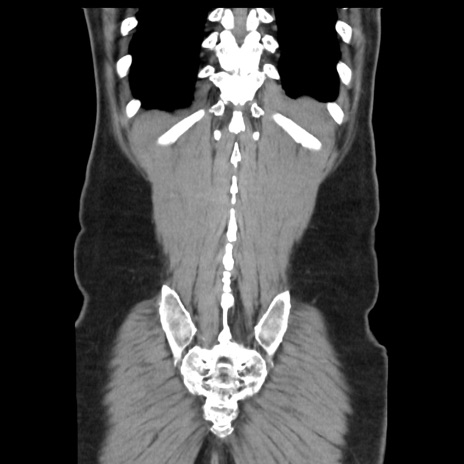

症例16(冠状断像)

【症例】 70歳代男性

【主訴】 腹痛、嘔吐

【現病歴】 約1ヶ月前より間欠的に腹痛と嘔吐あり、当院消化器内科を受診したところCTで多発する肝臓のLDAを指摘され、精査中であった。以降は消化器症状は安定していたが、2日前より嘔気と腹痛があり、同日より排便・排ガスが消失した。改善認めず、 本日、救急外来を受診した。